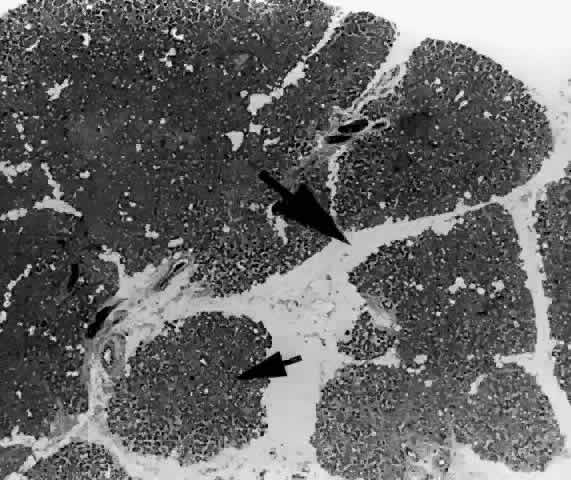

Each lobe of the lacrimal gland is separated into numerous lobules by interlobular fibrovascular connective tissue (Fig. 11). Each lobule, as seen by light microscopy, is composed of two units (Fig. 12): (1) the acinar unit (or secretory unit); and (2) the ductal system. The acinar units are further separated by intralobular fibrovascular connective tissue.

Fig. 11. Lacrimal gland architecture. Each lobe of the lacrimal gland is separated into numerous lobules by interlobular fibrovascular connective tissue. (H & E, original magnification × 5; Courtesy of Ralph Eagle, MD, Philadelphia, PA)

Fig. 12. Lacrimal gland. Each lobule is composed of acinar secretory units (above) and a ductal system. An interlobular duct is seen (lower right). (H & E, original magnification × 25; Courtesy of Ralph Eagle, MD, Philadelphia, PA)